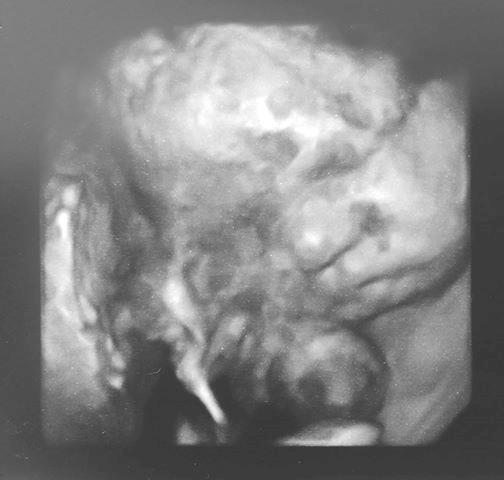

Update from Hanna and Scott: Mid transfusion check up today went well she looking good.. (blood transfusions have helped her a lot) 35 weeks tomorrow ekkk even came away with a 4D scan altho she didn't look impressed about it lol... also now have date for induction... 17th august so we are having her in 2 and a half weeks time !!!